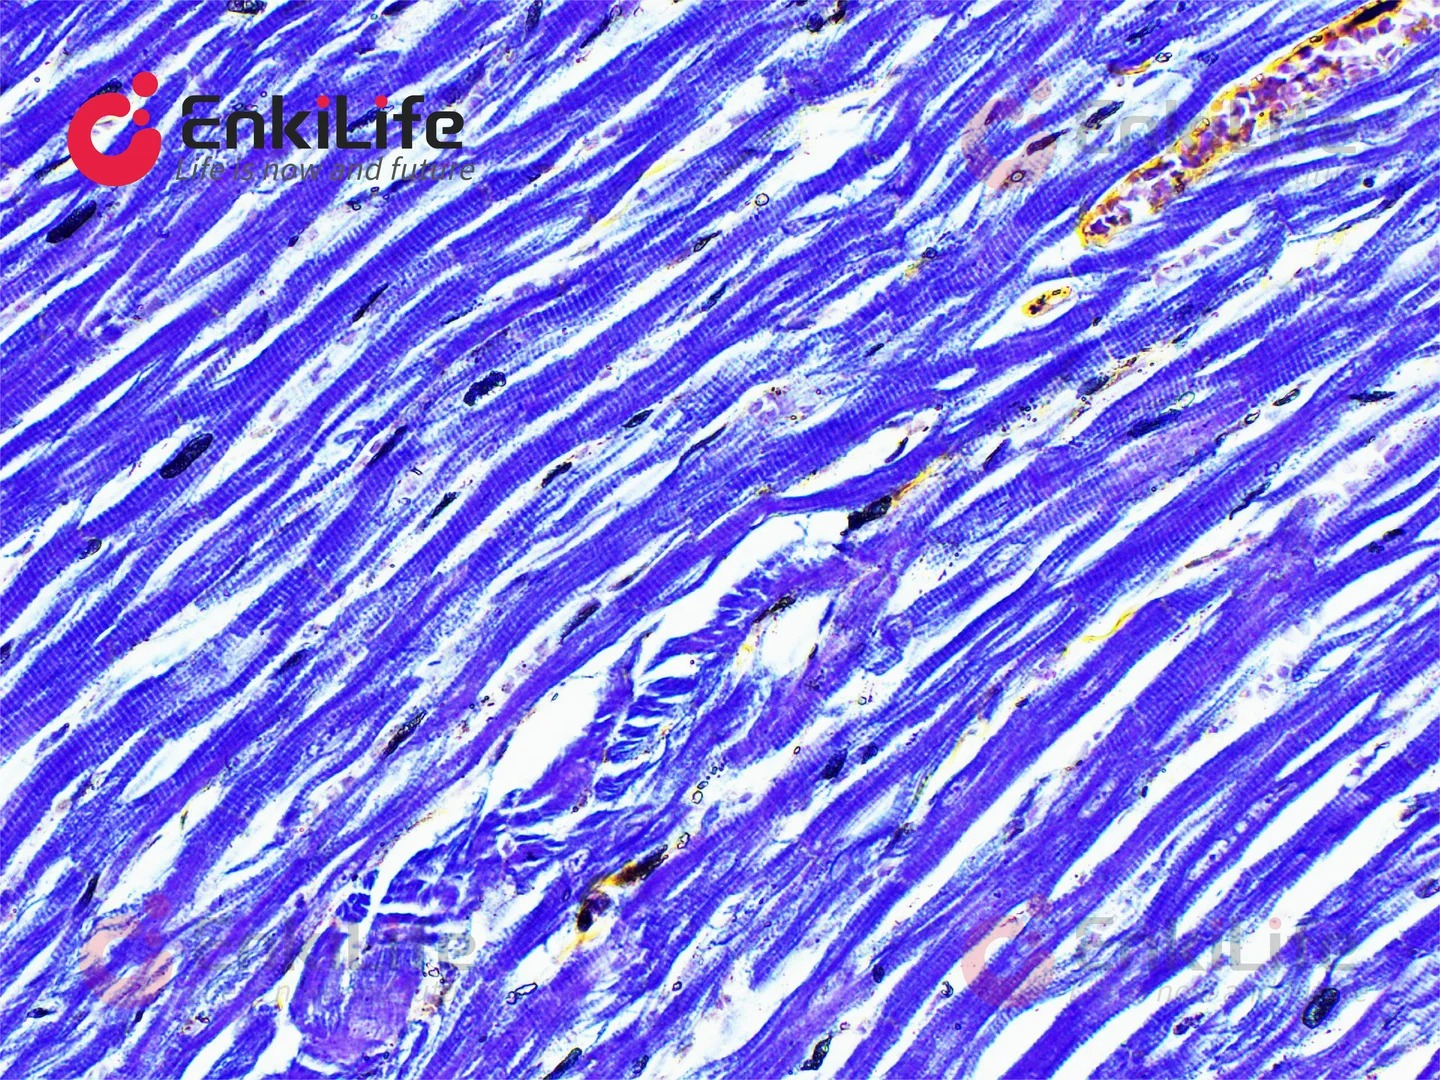

三、染色效果??

经过磷钨酸苏木素染色的切片,肌肉纤维会呈现出一种美丽的紫蓝色,就像是一条条精致的丝带,清晰地排列在组织中。神经纤维也会被染上淡淡的蓝色,和周围的组织形成鲜明的对比。而且这种染色方法还能显示出一些特殊的结构,比如肌肉中的横纹,这对于科研分析来说可是超级重要的线索呢。